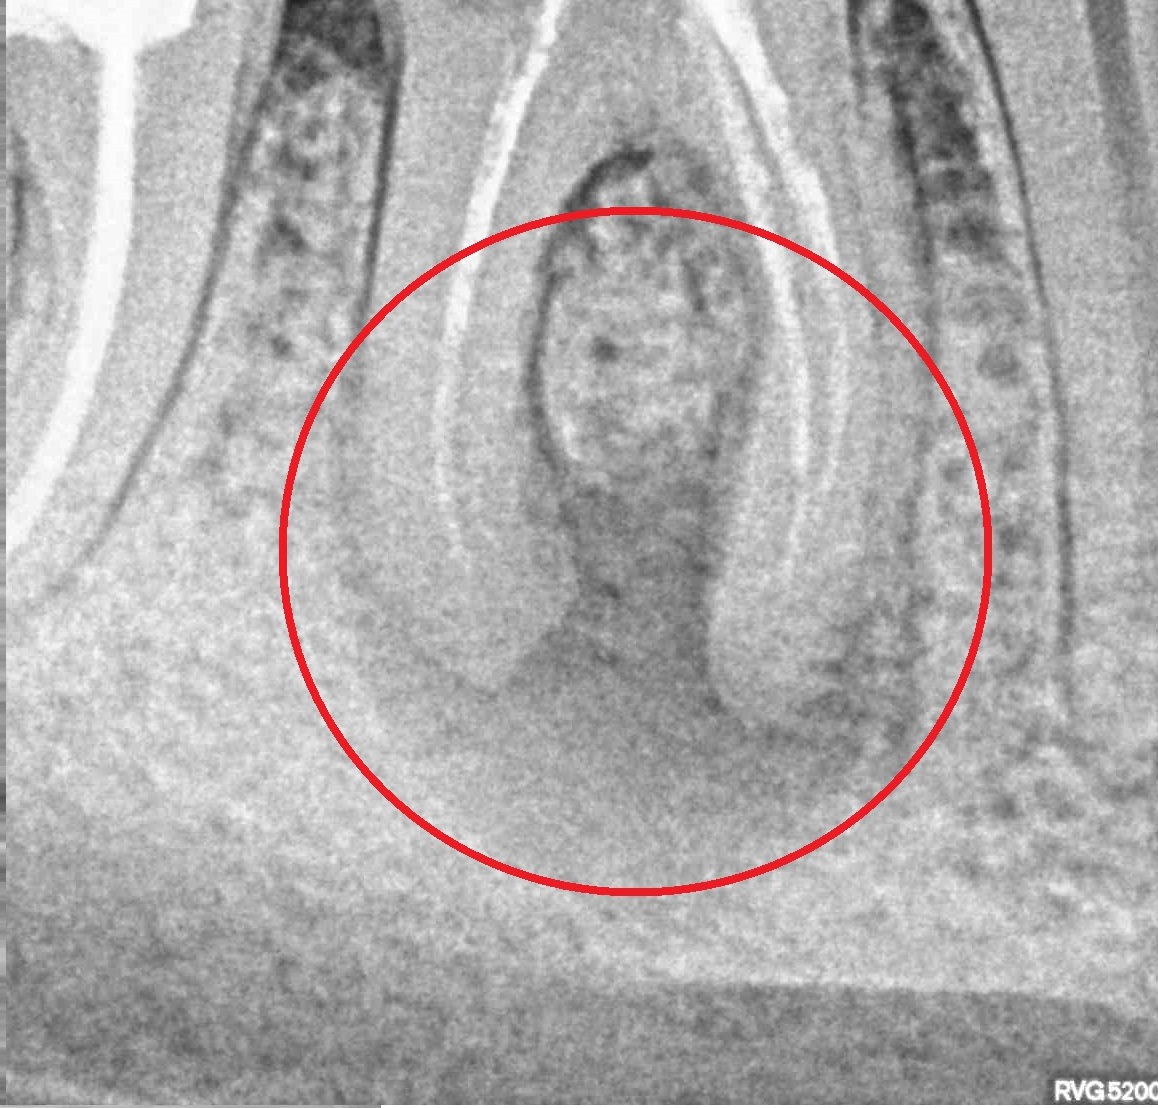

- Лечение периодонтита

Проблема

Пациент обратился в клинику с постоянными ноющими болями усиливающимися при накусывании.Решение

В нескольких клиниках было предложено удаление данного зуба. В нашей клинике такие зубы лечат. Пациенту было проведено эндодонтическое лечение данного зуба. Результат положительный, идет восстановление костной ткани.Оставьте заявку - перезвоним в течении 15 минут!